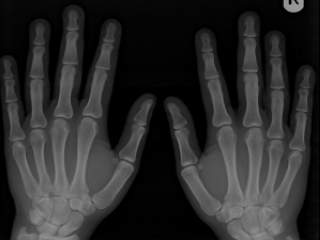

Iako postoji veoma veliki broj patoloških stanja koja primarno ili sekundarno zahvataju naše kosti, najčešći vid patologije jesu prelomi ili frakture. Razlozi koji dovode do preloma kosti su mnogobrojni, biohemijski, degenerativni, metabolički, idiopatski, maligni ali najčešće mehaničke prirode.

Bolest o kojoj se dosta priča poslednjih par decenija jeste osteoporoza. Osteoporoza je samo jedna od sistemskih bolesti koštanog tkiva koja se možže razviti u ljudskom organizmu. U pitanju je bolest koja se manifestuje malom koštanom masom i mikroarhitektonskim gubitkom tkiva kosti.

Period imobilizacije traje od 3 nedelje do par meseci, naravno u zavisnosti od vrste preloma i eventualnih komplikacija stanja.Težina preloma kostiju direktno odlučuje o brzini regeneracije. Posle nekoliko meseci ili godina nema tragova preloma na radiološkom pregledu.